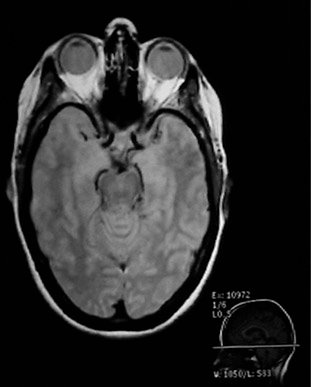

| Since the MRI uses proton NMR, it images the concentration of protons. Many of those protons are the protons in water, so MRI is particularly well suited for the imaging of soft tissue, like the brain, eyes, and other soft tissue structures in the head as shown at left. The bone of the skull doesn't have many protons, so it shows up dark. Also the sinus cavities image as a dark region.